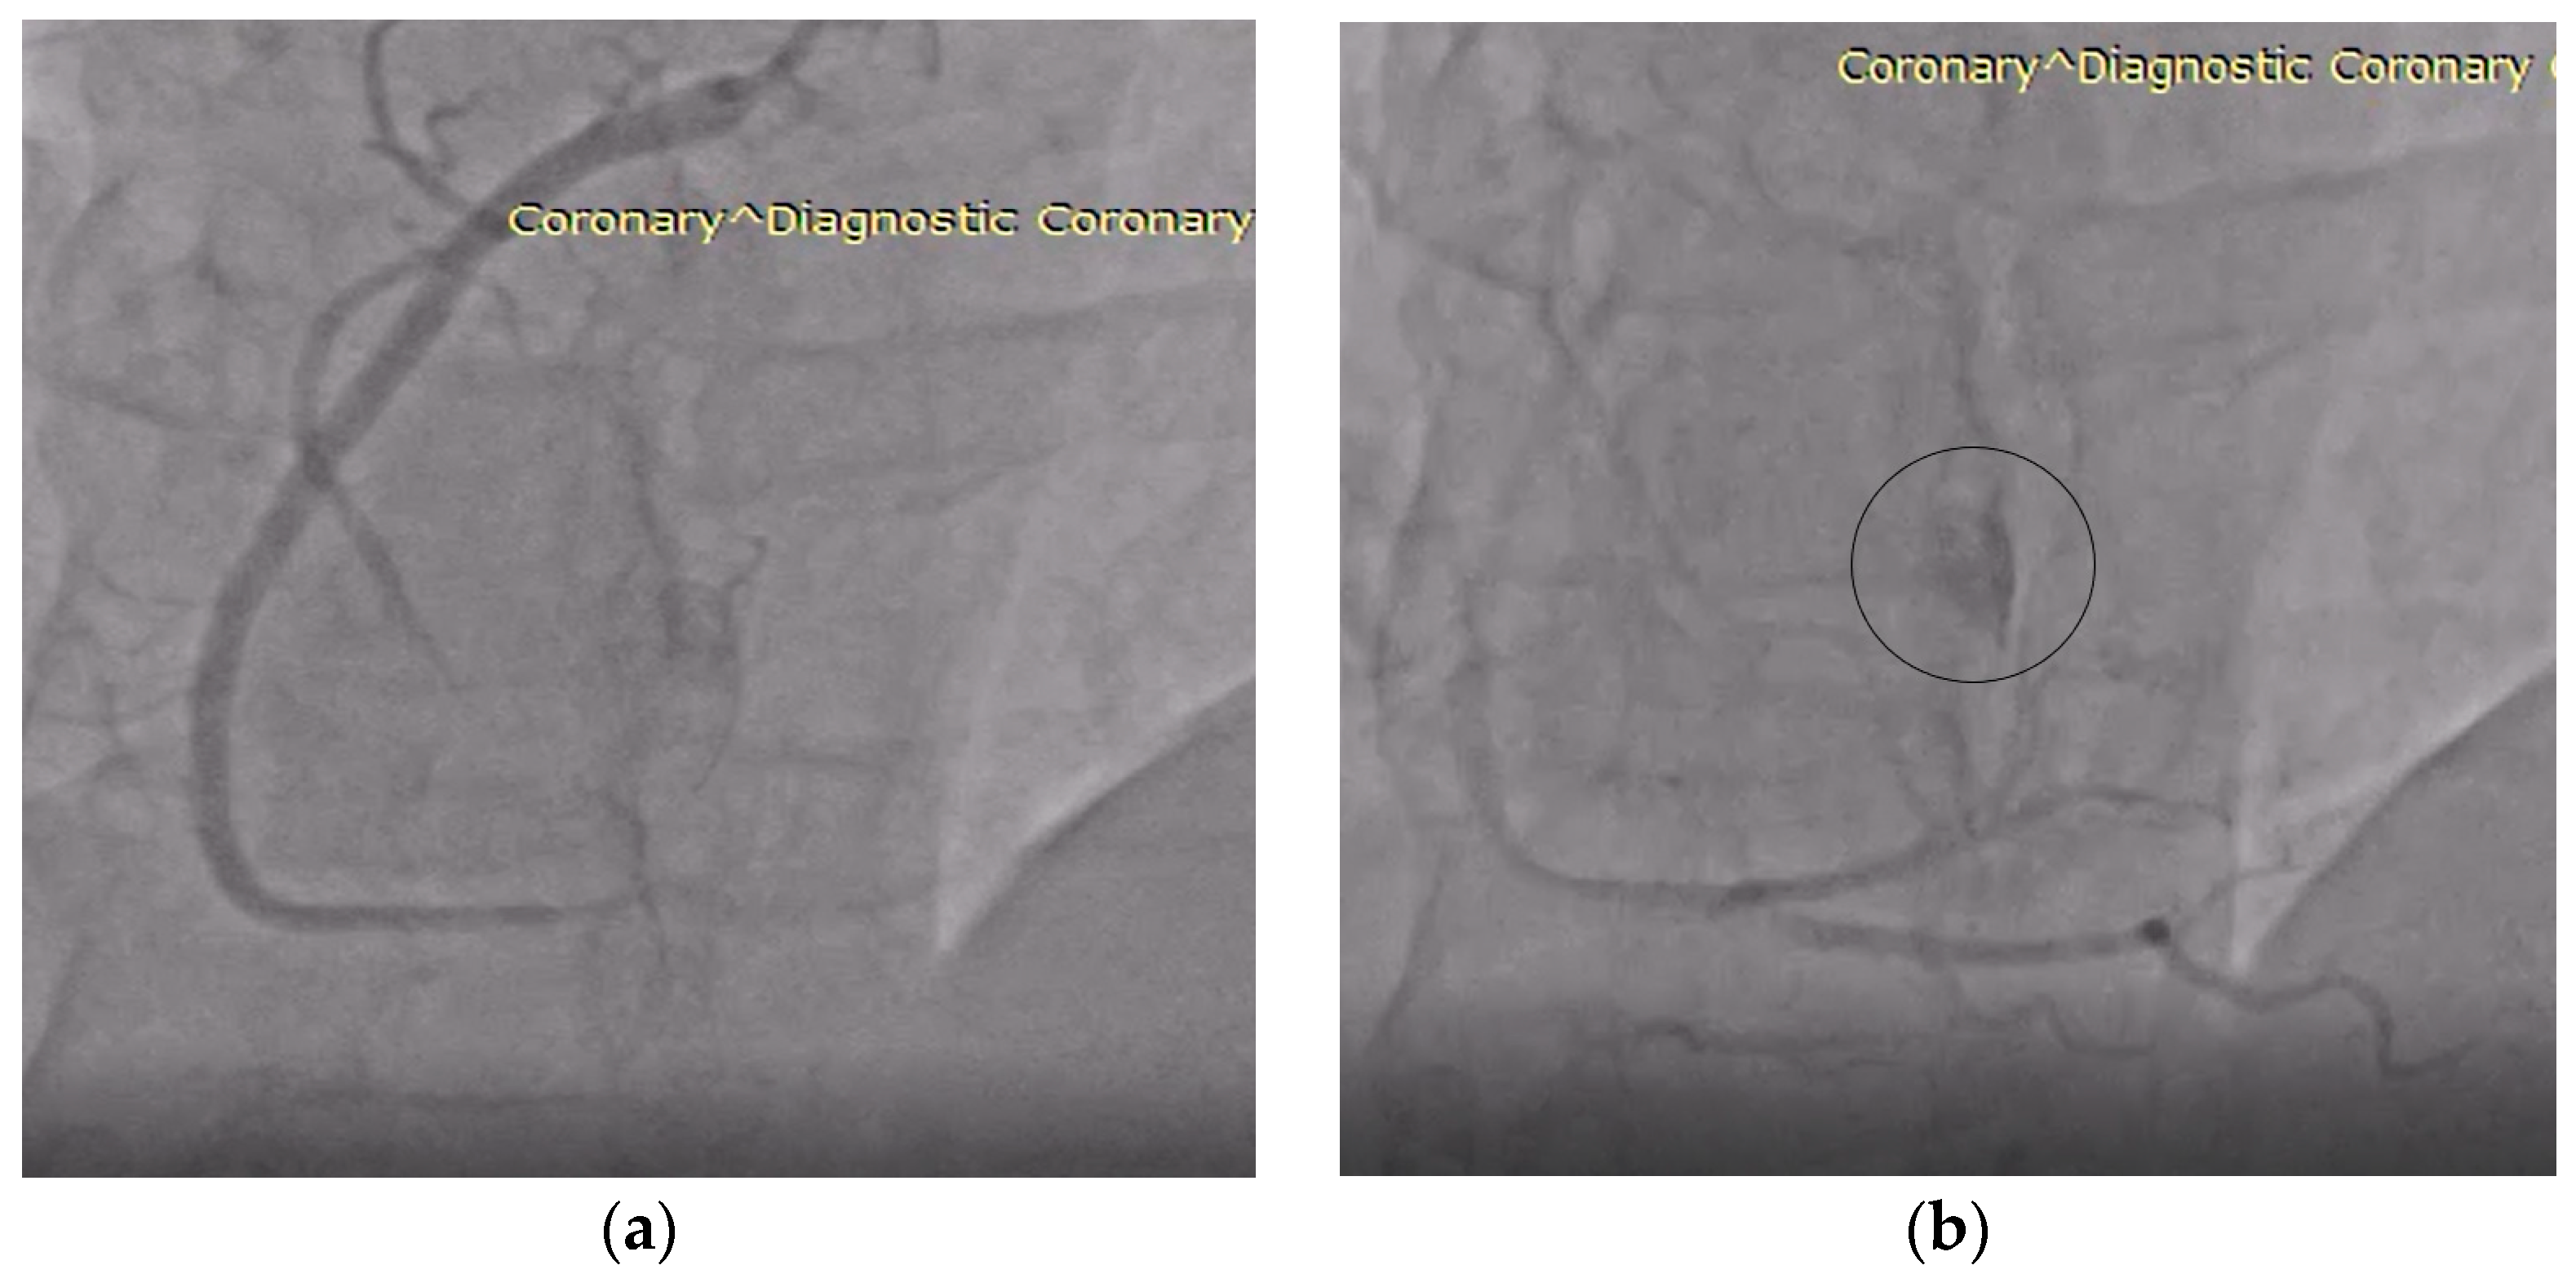

| Day 2 (hospital stay) | Coronary angiography: right-dominant system without stenoses; incidental fistulous connection draining into the right atrium, raising suspicion of a hypervascular lesion. |